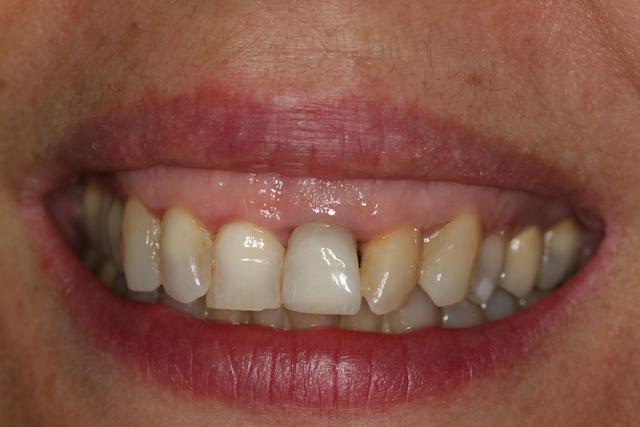

Essayage ce jour de la ceram pure, pouf trop grise.

Ai bien vérifié la teinte avant et après, c'est bien A1. (comme sur la 11) Avec un collet assez opaque, un bord incisif avec un aspect un petit peu crayeux.

Par contre un bon gris de la 21 "dent dévitalisée" difficile à retrouver sur le teintier (Shofu) type C2.